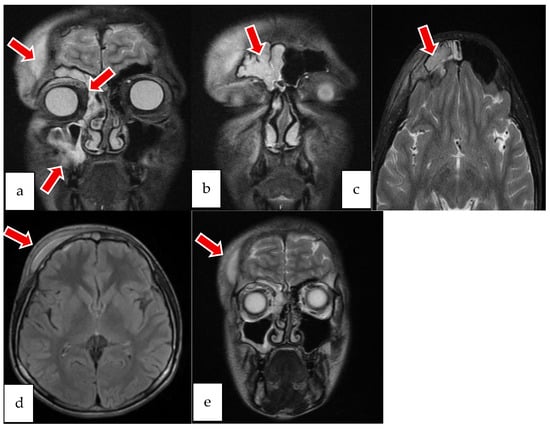

2.2. Case 2